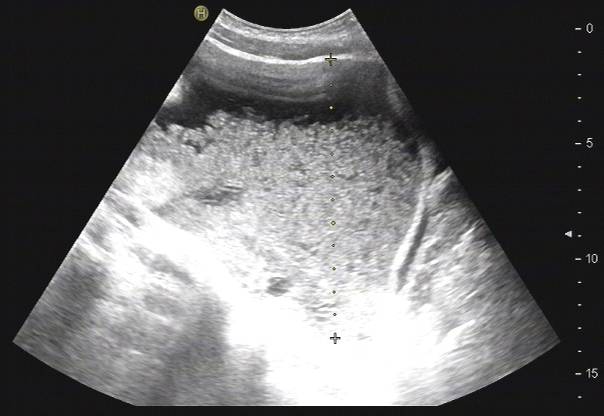

患者刘某,男性,34岁,于入院前2周因无明显诱因出现腹胀、纳差、腹围进行性增加来院就诊。查体:血压、体温、呼吸、脉搏正常,心肺无异常,腹部膨隆,腹软,全腹未触及明显压痛及反跳痛,肝脾触诊不满意,腹水征阳性,肠鸣音约3-4次/分钟,浅表淋巴结无肿大。腹部彩超检查结果如图1所示,可见密度不均匀腹腔积液,内见细光点回声随体位移动,初步考虑为结核性腹膜炎。

此图为腹部超声检查结果:B超可见密度不均匀的腹腔积液,内见细光点回声随体位移动。